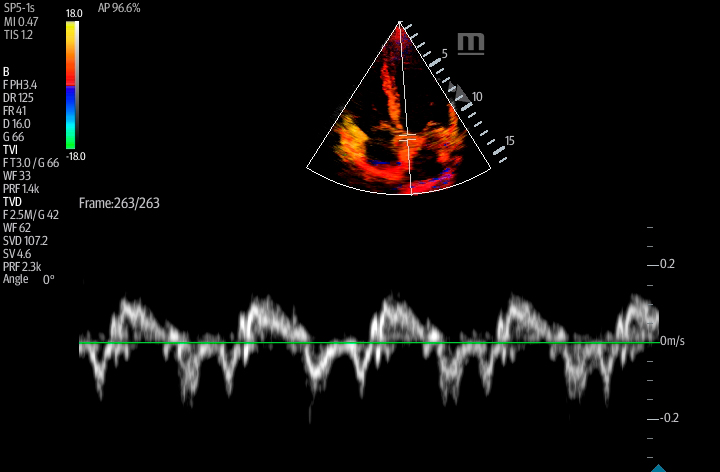

Smart VTI

Automated measurement of the Velocity Time Integral (VTI) and Cardiac Output (CO), enables rapid assessment of cardiac function. This software automatically locates color box and Pulse Wave Doppler (PW) sample line in real time. A graph of parameter trends for CO, Stroke Volume (SV) and VTI is produced to guide decision-making.